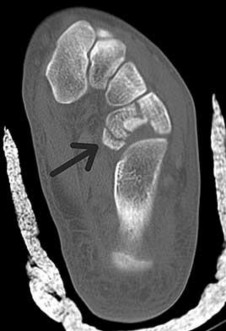

Tarsal coalitions occur when primitive mesenchymal cells fail to differentiate and form the

normal articular separations between the tarsal bones of the hindfoot. Overall incidence is difficult to determine because many affected people are minimally symptomatic or asymptomatic. Symptomatic tarsal coalitions typically present in adolescents as a painful flatfoot; however, there are a number of possible presentations, and occasionally symptoms do not appear until adulthood. Most tarsal coalitions are between the calcaneus and the navicular (CN) and the talus and the calcaneus (TC). Although most TC coalitions are across the middle facet, posterior facet coalitions do occur. Plain radiographic evaluation of suspected tarsal coalition is the mainstay for diagnosis. However, coalitions can be bony or fibrous, and making the diagnosis can be difficult. The addition of CT images to distinguish bony definition and MR images to decipher soft tissue can aid in diagnostics. Bony coalitions appear as definite bony bridging between the bones, while fibrous coalitions are suspected when distortion of the bony anatomy is seen. Bony coalitions are best seen on the oblique view (CN) and Harris axial view (TC). There are a number of secondary signs such as the anteater (AE) sign (elongation of the anterior process of the calcaneus as it extends to the navicular as seen on the lateral view [CN]). talar beaking (traction spur of the talar neck thought to result from abnormal stresses as seen on the lateral view [both CN and TN]), and the “C” sign (a continuous cortical contour from the medial talus to the sustentaculum tali [ST]) as seen on the lateral view (TC). A number of newer signs are not as well known, such as a broad mediolateral dimension of the navicular on the anteroposterior (AP) view (the

navicular is wider than the talar head [CN]), nonvisualization of the middle facet on the lateral view (TC), the brick sign (a normal ST is flat, but a distorted ST is enlarged and curved [CN]), and a tapered lateral navicular bone as seen on the AP view (the medial navicular [CN] is much thicker than the lateral navicular).

Figures 4a through 4j do not show any signs of a coalition.